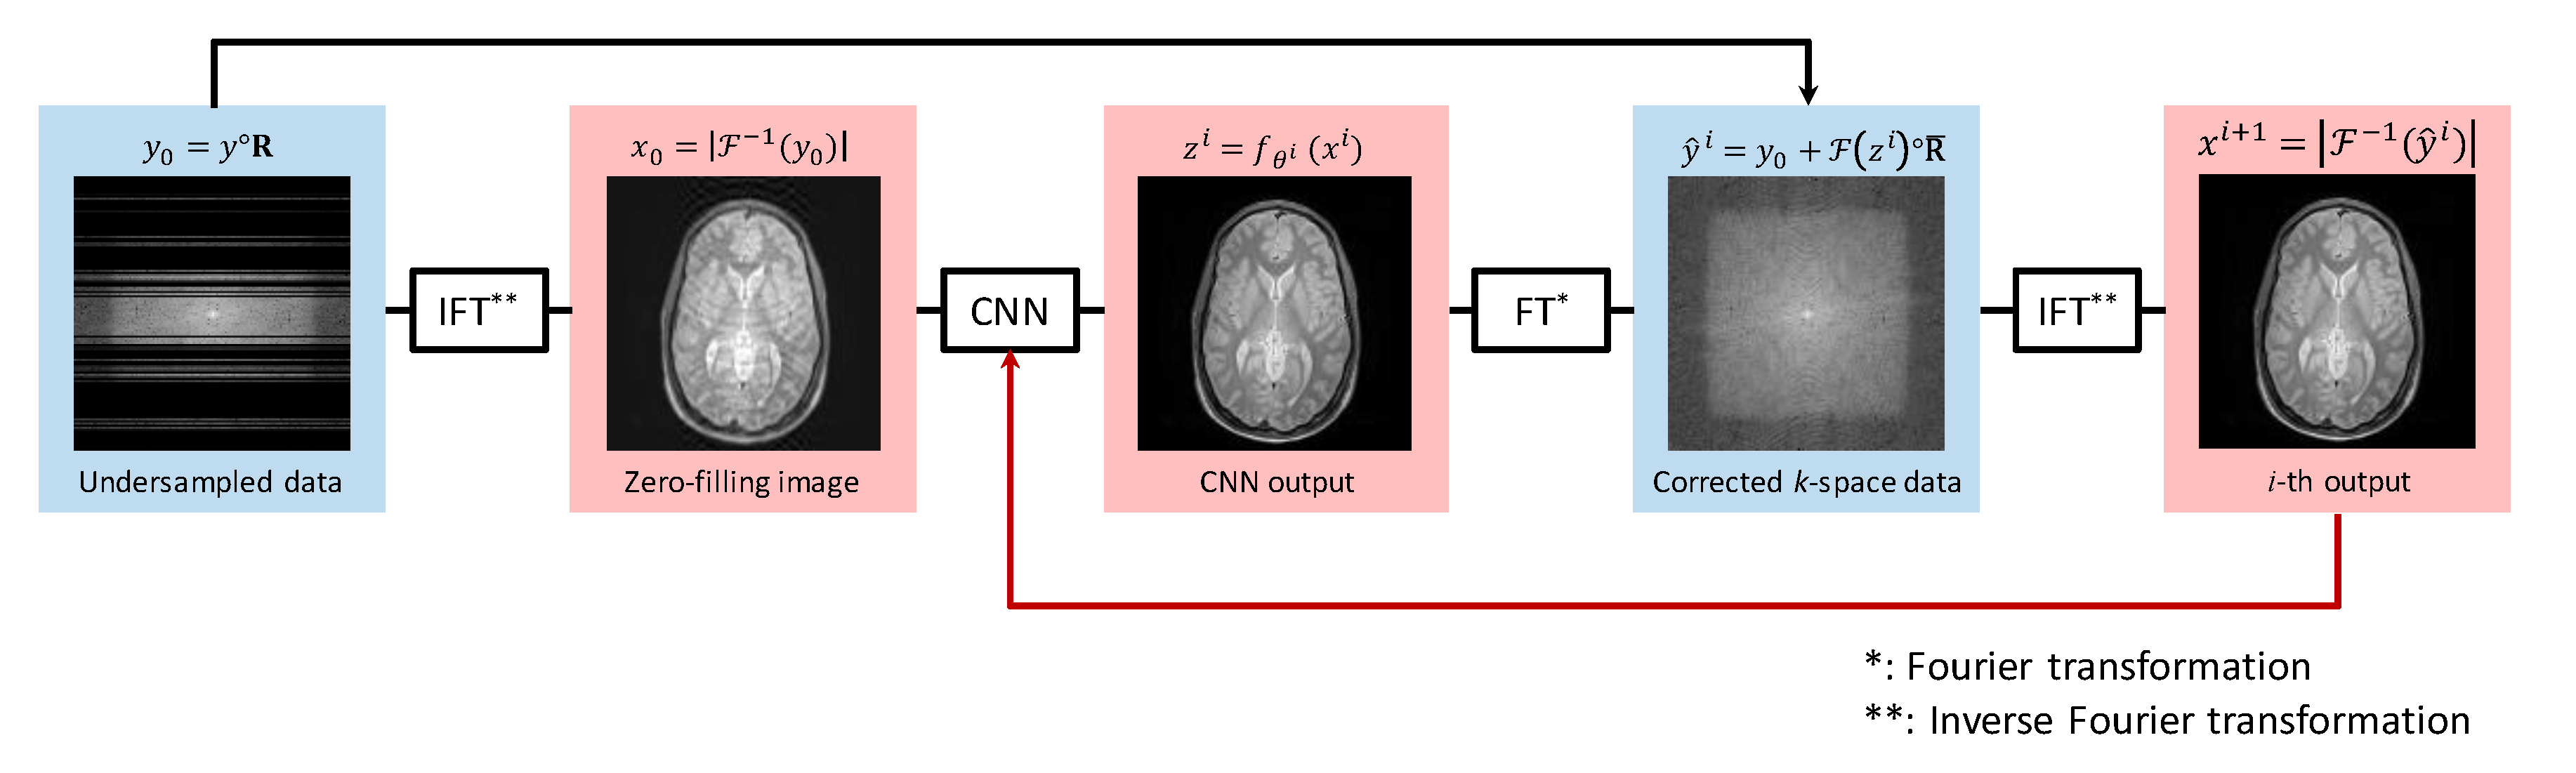

2.1. Proposed Method